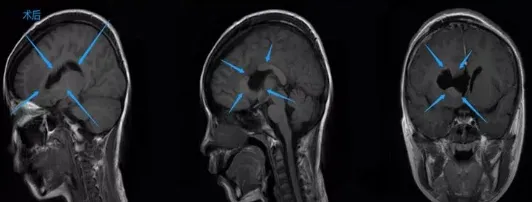

手术成功:肿瘤全切与快速康复

手术当日天气晴朗,仿佛预示转机。女儿术后送入ICU观察,巴教授告知手术顺利完成,肿瘤近乎全切。我激动得语无伦次,反复道谢。术后两天女儿转出ICU,未出现任何神经功能损伤。七天内她能独立行走,预期中的严重并发症均未发生。很快女儿恢复活泼状态,与病前无异。